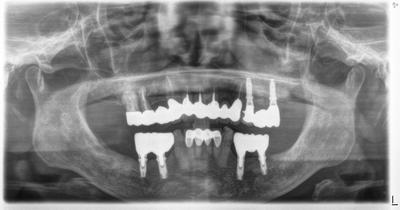

2021.02.19インプラント包括ケース

インプラントを含む包括診療ケース、術後17年、メインテナンス中。

治療終了後、コンポジットレジン充填以外ほとんど追加治療は行っていない。

使用インプラントはBiomet3i(アメリカ)、左側臼歯部はサイナスリフトを行っているが、移植骨は完全に置換し、患者さん自身の骨と区別がつかなくなっている。